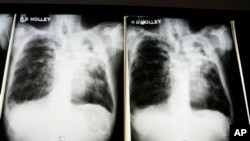

Proyek Olallo di London dibentuk untuk membantu tunawisma dari Eropa Tengah dan Timur agar dapat kembali mandiri, mendapatkan tempat tinggal dan pekerjaan. Tetapi kegiatan amal itu justru berkembang untuk melayani kebutuhan lain yang mendesak, yaitu menanggulangi tuberkulosis (TB) dalam komunitas migran Inggris.

Rimgaudas Planecinas baru saja menyelesaikan pengobatan 18 bulan untuk memerangi TB yang kebal multi-obat, atau MDR-TB.

Pendatang dari Lithuania ini merasa sulit menggambarkan pengalamannya. Katanya pengobatan itu membuatnya sakit dan mempengaruhi penglihatannya. Ia masih menderita setelah pengobatan selesai.

Pada tahun 2011 lebih dari 400 kasus TB kebal obat dilaporkan di Inggris. Dibanding kawasan lain di dunia, angka itu kedengaran tidak besar, tetapi angka itu merupakan peningkatan 26 persen dari tahun lalu.

Sebagian kasus TB kebal obat di Inggris dapat ditelusuri ke bagian timur benua itu, di mana jumlah penderita tertinggi di dunia ditemukan. TB biasanya menjadi kebal terhadap obat ketika dosis antibiotik terganggu. Tetapi tes-tes di Eropa Timur menunjukkan TB kebal obat sekarang menular langsung dari orang ke orang.

Ibrahim Abubakar, pakari Tuberkulosis dari University College London, mengatakan, "Kami kira sekitar sepertiga populasi yang belum pernah diobati dengan antibiotik sekarang menderita MDR-TB di kawasan Eropa Timur. Ini sangat mengkhawatirkan karena berarti mereka benar-benar terjangkit MDR-TB dari orang lain, bukan karena mereka salah menggunakan obat."